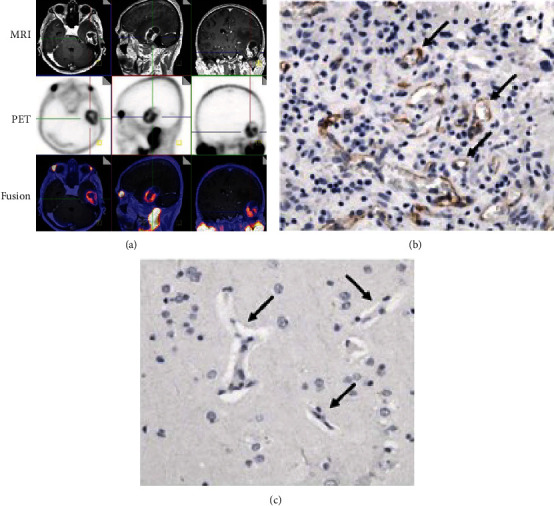

Results: Tissue studies demonstrated PSMA expression in tumor vascular endothelial cells, without expression in normal brain tissue, though the extent and intensity of staining varied by anti-PSMA antibody and methodology. Most included studies reported on gliomas, which showed strong PSMA ligand uptake and more favorable tumor to background ratios than other PET tracers. There are also case reports demonstrating PSMA ligand uptake in prostate cancer brain metastases, nonprostate cancer brain metastases, and meningiomas. We also review the properties of the various PSMA-binding radiotracers available. Therapeutic and theranostic applications of PSMA-binding tracers have been studied, including labeled alpha- and beta-ray emitting isotopes, as well as PSMA targeting in directing MRI-guided focused ultrasound.

Abstract Image